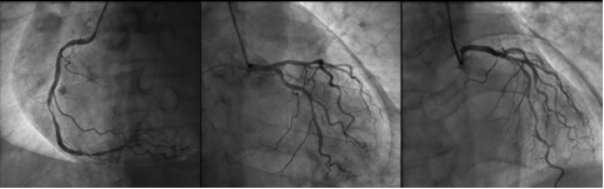

1 资料与方法患者男性,70岁,因“胸闷3 d,加重伴呼吸困难1 d”于2019年9月13日入外院。患者3 d前无明显诱因出现胸闷,伴全身乏力,夜间睡眠差(可平卧),初未予重视,1 d前胸闷加重,伴呼吸困难、运动耐量明显下降、大汗淋漓、皮肤湿冷,至外院就诊,查心电图(图 1):交界性逸搏,肢体导联低电压,Ⅰ、Ⅱ、Ⅲ、aVF、V4、V5、V6导联ST段抬高0.15 mV~0.4 mV,aVR、aVL、V1导联ST段压低0.05 mV~0.2 mV,aVL、V1导联T波倒置;心肌酶:CKMB 27.1 U/L,NT-proBNP 3 298 pg/mL。外院考虑不排除急性心肌梗死导致的心源性休克,经口气管插管接呼吸机辅助通气后为进一步诊治转入本院。患者家属否认患者有外科手术、外伤、气胸及哮喘发作史,起病以来无畏寒、高热,大、小便正常,既往1年余前因“反复咳嗽伴咳血丝痰”在外院诊断为右肺门鳞癌,合并高血压病、2型糖尿病,经依托泊苷+顺铂化疗,具体剂量不详。2019-09-07复查胸部CT提示右肺病灶较前缩小。体格检查:体温35ºC,血压86/43 mmHg,心率53次/min,呼吸15次/min(经口气管插管呼吸机辅助呼吸),神志昏迷,双侧颈静脉怒张,气管居中,桶状胸,胸廓对称,双肺呼吸动度对称,叩诊呈清音,听诊呼吸音清,双肺未闻及干湿性啰音,心前区无隆起,叩诊心界消失,心音低弱遥远,桡动脉、股动脉搏动可触及。入院后复查心电图(图 2):心房颤动,肢体导联及胸导联低电压,各导联ST-T改变较前相似,未见明显动态演变。血常规:白细胞1.27×109/L,中性粒细胞1.15×109/L,血红蛋白98 g/L,降钙素原43.01 ng/mL,超敏肌钙蛋白Ⅰ 0.048 ng/mL。急诊冠脉造影(图 3):左前降支近段轻度狭窄,中段心肌桥,收缩期重度狭窄,左回旋支远段中度狭窄,右冠中段重度狭窄,TIMI血流均为3级。患者超敏肌钙蛋白I未见明显升高,冠脉血流通畅,排除急性心肌梗死引起的ST段抬高。心脏彩超:气体干扰较大,仅能从剑突下观察,心包腔内未见积液。胸片(图 4):纵隔内可见条状透亮带,心影周围可见一弧形透亮带,考虑心包积气、纵隔气肿。入院诊断为“①心包积气、②纵隔气肿、③右肺鳞癌”,经剑突下途径行心包穿刺置管术+闭式引流术,术后液封瓶内见气体逸出,患者血压较前逐渐上升。完善胸部CT(图 5):右侧肺门增大,右主支气管与上叶支气管壁交界处见小缺损,考虑支气管破裂,心包、纵隔、胸腔及腹腔积气。纤维支气管镜(图 6)检查:可见右主支气管距隆突约1 cm处见破损,破损处周围组织呈白色,不排除癌组织浸润可能。病因考虑为右肺门鳞癌浸润右主支气管,穿孔后经纵隔与心包腔形成瘘道,引起心包积气。经过上述治疗后患者血流动力学稳定。

| 图 3 冠脉造影提示冠脉轻至重度狭窄,心影周围可见弧形透亮带 |

该例患者主要临床症状为胸闷伴有呼吸困难,体格检查时患者存在血流动力学不稳定及意识障碍,结合心电图、心肌酶结果,考虑急性心肌梗死导致心源性休克的可能,行急诊冠脉造影发现患者冠脉血流通畅,排除急性心肌梗死,同时在冠脉造影过程中发现患者心影周围存在弧形透亮带,转入ICU后行胸片检查证实心包积气的诊断。心包积气产生的原因主要为医源性操作(如心包穿刺术、胸腔穿刺术、射频消融术及埋入式起搏器植入术等)、心包炎、心包与邻近含气器官之间的瘘管形成以及外伤,其中正压通气亦是原因之一[9-12]。正压通气可迅速增加心包积气容积及加快其增长速度,从而加重心包填塞。该患者入外院后行经口气管插管接有创呼吸机辅助呼吸,本院胸部CT与支气管镜检查可见右主支气管破口,破损处周围组织呈白色,不排除癌组织浸润可能,考虑为右肺门鳞癌浸润右主支气管,穿孔后经瘘道与纵隔及心包腔相连,引起心包积气。